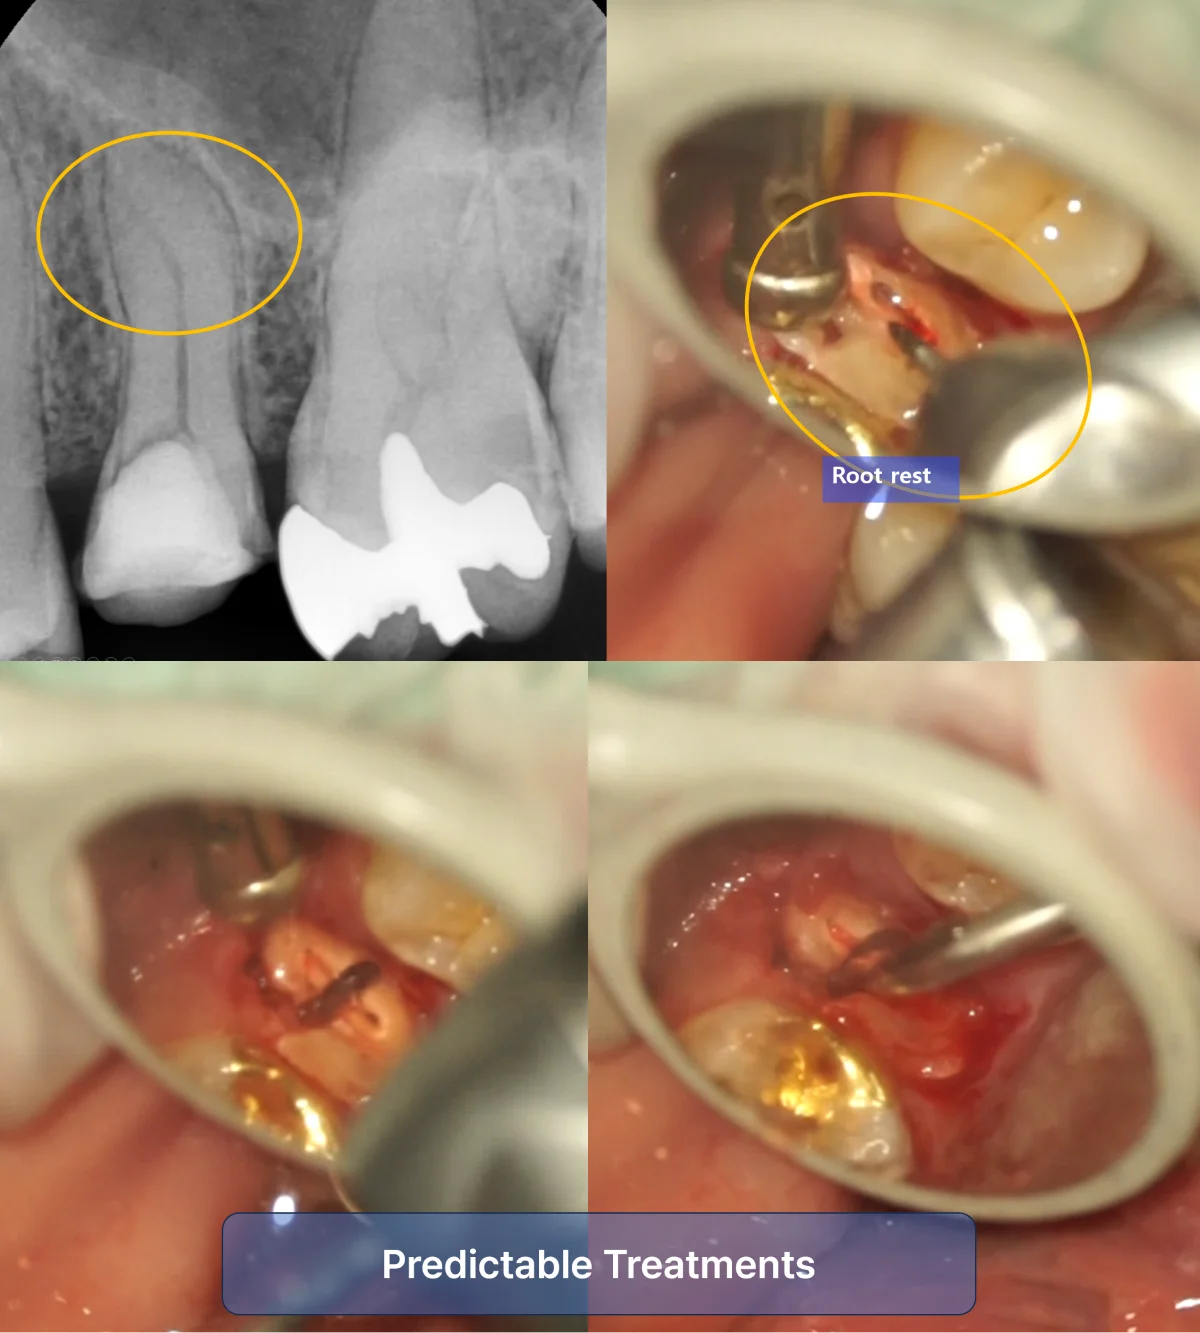

Predictability in Treatments

Consider the extraction of a root of the upper premolar. The difficulty of this procedure can significantly vary depending on whether you can see the surgical site properly. Without clear visibility, you might rely on tactile sensation, leading to unpredictable and prolonged procedures. However, with a mirror providing a clear view, extractions can be performed more predictably and within a set protocol.

Due to hypertrophy of the apical part of the maxillary second premolar, extraction using an elevator is impossible. Extraction was performed using a root picker after separating the buccal and lingual sides with the aid of a dental mirror to ensure visibility.